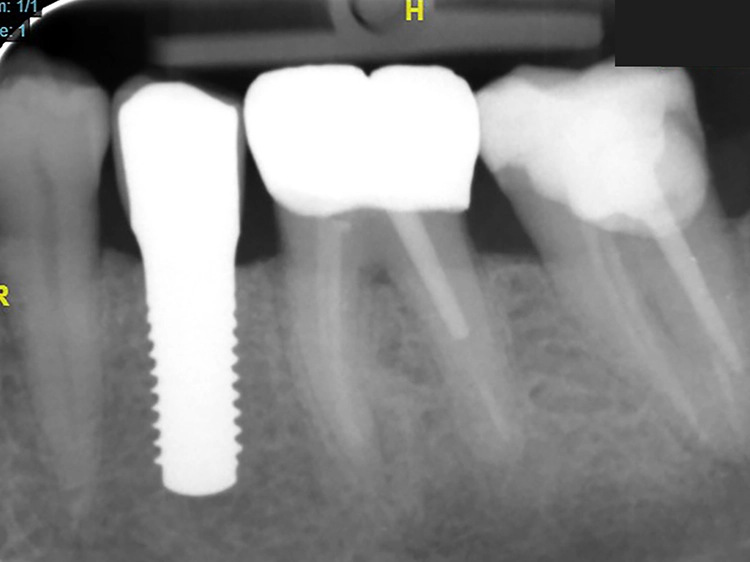

Auch wenn die deutliche Mehrheit der bisher veröffentlichten Daten Bezug auf einteilige Implantatsysteme aus der Hochleistungskeramik Zirkonoxid nimmt und bislang wissenschaftliche Daten zu Zirkonoxidimplantaten mit zweiteiligem Implantatdesign noch limitiert sind, so lässt sich festhalten: „Eine von unserer Studiengruppe durchgeführte Meta-Analyse, in die klinische Studien integriert wurden, hat gezeigt, dass das Implantatdesign einteilig gegenüber zweiteilig keinen Einfluss auf die Überlebensraten hat“, betont Dr. Röhling. „Auch wenn sich Meta-Analysen zur Schätzung der Gesamtüberlebensraten derzeit auf 1- und 2-Jahres-Daten beschränken, berichteten einzelne Studien über längere klinische Nachbeobachtungszeiträume.

Für kommerziell erhältliche Zirkonoxid-Implantate liegen inzwischen klinische Daten für Nachuntersuchungszeiträume von bis zu fünf Jahren funktioneller Belastung mit Überlebensraten von 95 Prozent vor. Es gibt genug Daten und aus unserer Sicht genug klinische Erfahrung, dass zweiteilige Konzepte mit Zirkonoxidimplantaten empfohlen werden können.“

Die Oberflächen sind sehr gut untersucht und bei einteiligen und zweiteiligen Implantaten gleich, „das heißt, einteilige und zweiteilige Zirkonoxidimplantate weisen den gleichen Grad an Osseointegration und biologischer Integrität auf“, erklärt der Fachmann. Auch zweiteilige Keramikimplantat-Verbindungen von führenden Herstellern seien mittlerweile wissenschaftlich untersucht und für die klinische Anwendung als geeignet eingestuft, so dass sich schlussfolgern lässt: „Zweiteilige Behandlungskonzepte sind ebenso praxistauglich und der Expertenkonsens lautet, dass das zweiteilige Zirkonoxidimplantatkonzept nach korrekter Indikationsstellung und entsprechender Patientenaufklärung für die klinische Anwendung geeignet ist.“ Kritisch merkt Dr. Röhling an, dass es von Seiten der Industrie unterschiedliche Produktionsstandards und Qualitätskontrollen gibt, was wiederum direkten Einfluss auf die Verlässlichkeit der Keramikimplantate und der prothetischen Verbindung hat („Das ist in diesem Zusammenhang problematisch“).